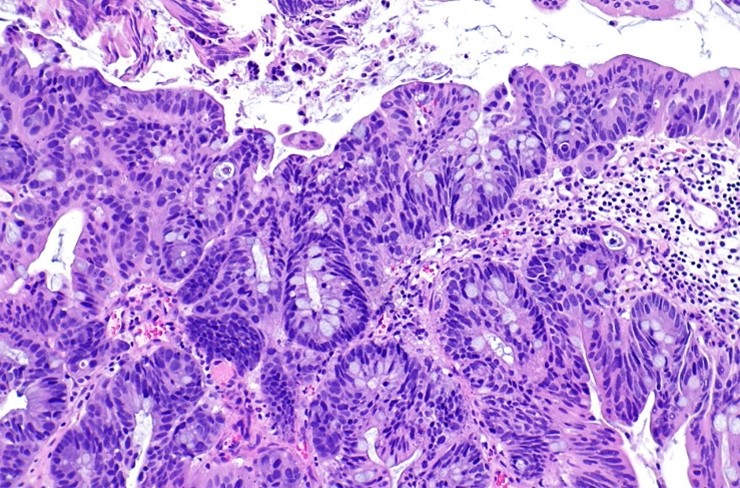

Вторым принципиальным различием поверхностных опухолей является их клеточное строение. На сегодняшний день современная онкоурология умеет прогнозировать возможное течение опухолевого процесса в зависимости от строение опухолевой клетки. Опухоль с низкой степенью злокачественности маркируется как «G1» или «low grade», а опухоль агрессивного течения, как «G3» или «high grade». Существует ещё опухоль «in situ» или карцинома in situ, т.е. стелящаяся опухоль, которая имеет агрессивный характер течения и выделяется гистологами отдельным термином.

Цитологическое исследование мочи:

Биопсия мочевого пузыря

Морфологическое исследование образцов, полученных после трансуретральной резекции и биопсии, является ключевым этапом в диагностике и определении стратегии лечения рака мочевого пузыря. Строго рекомендуется налаживать тесное взаимодействие между урологом и специалистом по морфологии. В клинике Хадасса самая современная патоморфологическая лаборатория, которая позволяет максимально точно провести диагностику биопсийного материала и точно поставить диагноз.